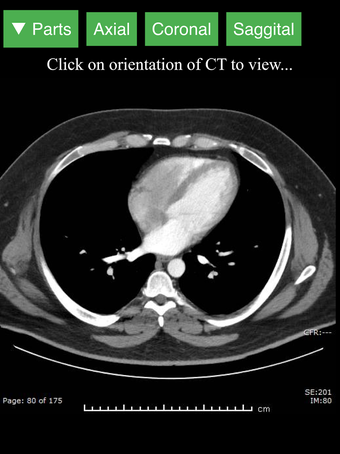

Radiology CT Viewer - полезный инструмент для врачей, медицинских студентов, радиологических техников и других медицинских специалистов, которые хотят узнать больше о человеческом теле и его анатомии. Приложение содержит подробные сечения наиболее важных частей тела. Кроме того, оно содержит интерактивную 3D-модель, которая позволяет вращать, увеличивать и перемещать камеру вокруг изображения, чтобы получить лучший обзор анатомии.

Если вы ищете инструмент, который поможет вам узнать больше о человеческом теле, Radiology CT Viewer - отличный выбор. Он содержит подробные иллюстрации и интерактивную 3D-модель.